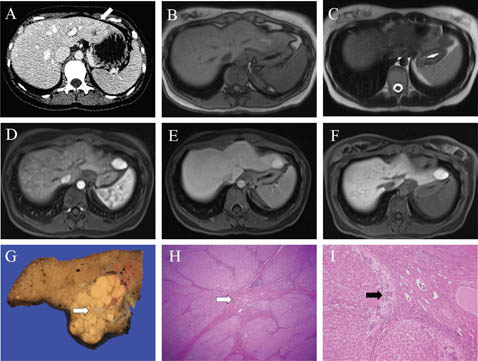

Fig 5

Figure 5. Representative images of hepatic epithelioid hemangioendothelioma. A. Transverse ultrasound image of the liver demonstrates a centrally hyperechoic lesion with a thin hypoechoic halo (“targetoid” appearance) in the right lobe of the liver with multifocal peripheral targetoid, heterogeneous and hypoechoic lesions involving both lobes (not shown). B and C. These lesions show low signal on the T1 weighted image (B) and intermediate to high signal on the T2 weighted image (C). One lesion in segment 7 at the subcapsular border is associated with focal capsular retraction (*). D, E, and F. Following gadolinium administration, the lesions show targetoid peripheral enhancement during the arterial (D) and portal (E) phases, and centripetal fill-in on the delayed phase (F). G. A representative slice of liver from a complete total hepatectomy of a separate patient shows multiple small red-brown lesions (white arrow) scattered throughout the parenchyma grossly. H and I. Bland epithelioid and spindled cells (I) are embedded in a fibrous and myxohyaline background (H). Slides are stained with Hematoxylin and Eosin. Total image magnification: H - 25X; I - 400X.

EHE is most commonly identified as coalescent, peripheral, target-like hepatic nodules with capsular retraction on a normal liver parenchyma background. Calcification is uncommon. Ultrasound is nonspecific; nodule echogenicity is variable, often hypoechoic (54). Unenhanced CT is also nonspecific, demonstrating hypoattenuating nodules. A ring or target appearance is common on MRI and CT, with 2 or 3 rings of differing enhancement/intensity. A 3-ring lesion consists of a dominant central non-enhancing or delayed enhancing fibrous myxoid stroma, which may demonstrate necrosis, an enhancing inner peripheral ring of proliferating tumor cells, and an outer avascular non-enhancing rim of tumor infiltrating into sinusoids and portal branches (5557). On T1WI, nodules are typically markedly hypointense centrally, with a less hypointense peripheral rim. On T2WI, small nodules are typically hyperintense, with larger lesions demonstrating a target pattern of central hyperintensity, a thin inner peripheral hypointense ring, and a hyperintense outer ring (56). Nodules may demonstrate a “Lollipop” sign; a well-defined, predominantly hypoenhancing nodule representing the spherical candy portion, and thrombosis within an associated vein, terminating smoothly at the edge or within the lesion rim, representing the stick (58).